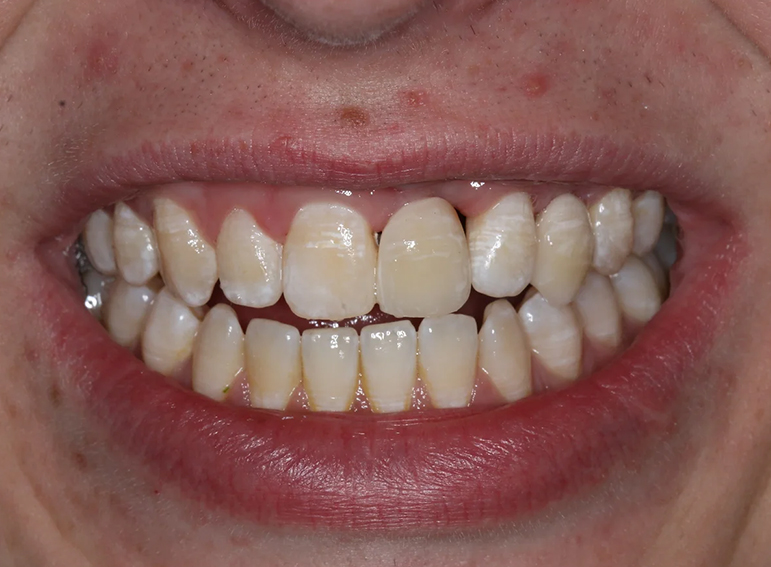

Replacement of 2 lateral incisors in a patient with hypodontia.